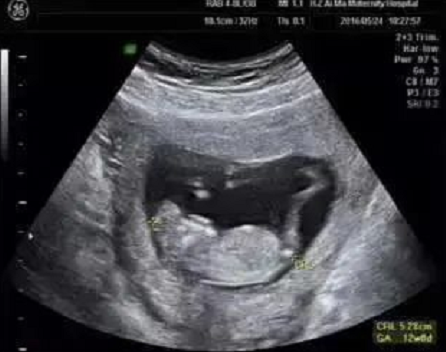

在为孕妈妈们做NT检查的同时,对于胎儿的结构也进行了详细的检查,并且发现了多例胎儿严重结构缺陷。

检查选在孕11~13周+6天进行,相当于头臀长45-84mm时测量,超过84mm检查结果会不准确。